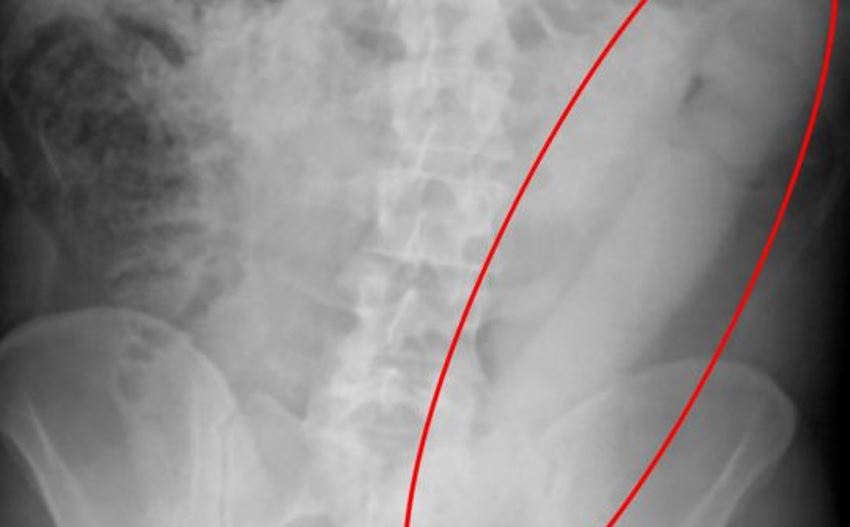

Dokter pun kemudian melakukan tindakan X-Ray. Dan nggak disangka, di dalam perutnya ditemukan benda aneh sepanjang 58 cm.

Setelah ditelusuri lebih dalam, ternyata benda yang bersarang di perut pria itu adalah sebuah dildo.